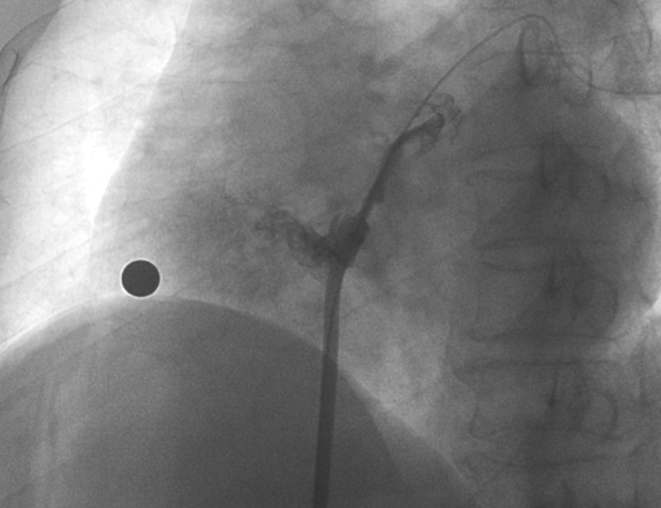

造影顯示長隧道型PFO

在本次植入手術(shù)中,接受介入封堵術(shù)的是一名卵圓孔未閉(長隧道型)的患者?;颊?0歲,男性,7年前曾診斷腦梗死,此次因新發(fā)腦梗死入院,無房顫及頸動脈狹窄;經(jīng)胸心臟超聲和心臟聲學(xué)造影檢查提示卵圓孔未閉,Valsalva動作后心房水平大量右向左分流。經(jīng)儲慧民教授團(tuán)隊評估,結(jié)合相關(guān)病史并考慮PFO及不明原因卒中,遂決定對患者開展經(jīng)皮PFO封堵術(shù)。

術(shù)中造影顯示患者為PFO且長隧道型,目前市場上已商業(yè)化的PFO封堵器難以滿足該患者解剖結(jié)構(gòu)封堵需求。迪創(chuàng)醫(yī)療自主研發(fā)的OmniSeal PFO封堵器自適應(yīng)性雙盤貼合設(shè)計能廣泛適應(yīng)不同PFO隧道長度的解剖結(jié)構(gòu)和形態(tài),其雙盤外包覆式阻流和隧道內(nèi)填充阻流相結(jié)合的雙重阻流設(shè)計,可為此患者實現(xiàn)有效封堵。與此同時,OmniSeal首創(chuàng)的完全可穿刺式設(shè)計,也為此患者最大程度地保留了房間隔區(qū)域穿刺通道,以實現(xiàn)全兼容未來可能的左心系統(tǒng)二次介入術(shù)。術(shù)終造影和心臟超聲顯示封堵完全、效果良好。作為OmniSeal的首例臨床應(yīng)用,本次手術(shù)的順利完成和優(yōu)異效果充分體現(xiàn)了產(chǎn)品的設(shè)計創(chuàng)新優(yōu)勢。